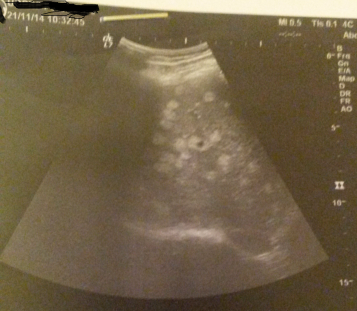

Жесть, вот меня сейчас в пот кинуло как прочитал "опухоли печени" меня эта тема в последнее время колбасит. Т.к. на узи показали множественные гипоэхогенные образования. Может у меня рак уже. Хотя делал мрт и кт с контрастами там ничего не увидели, а на фото узи очевиды образования. Узи перепроверял три раза, в трех разных клинках, включая Бакулина И.Г. все тоже самое.

Бакулин кстати тоже руками разводит высказали предположение на паразитов типо черви которые печень жрут. Сдал все анализы не подвердилось. Ни кто ни чего не может сказать мне, что за хр&нь с печенью...

Вот такая картина маслом. Сергею, (совок) написал тоже в тему по этой фотке.

- Вложения

- 14517.png (193.38 КБ) 5208 просмотров